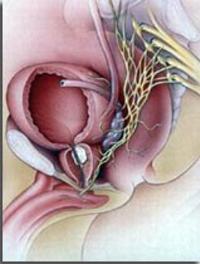

AFU – Paris. Dans le cancer de la prostate, la curiethérapie par implants d’iode 125 est réservée aux formes cliniques de pronostic [...]

Une équipe états-unienne montrait il y a quelques années que la prostatectomie radicale n’était pas associée à une réduction significative [...]

L’attentisme vigilant est proposé parfois à la place de la prostatectomie radicale pour les cancers localisés de la prostate. Cette [...]